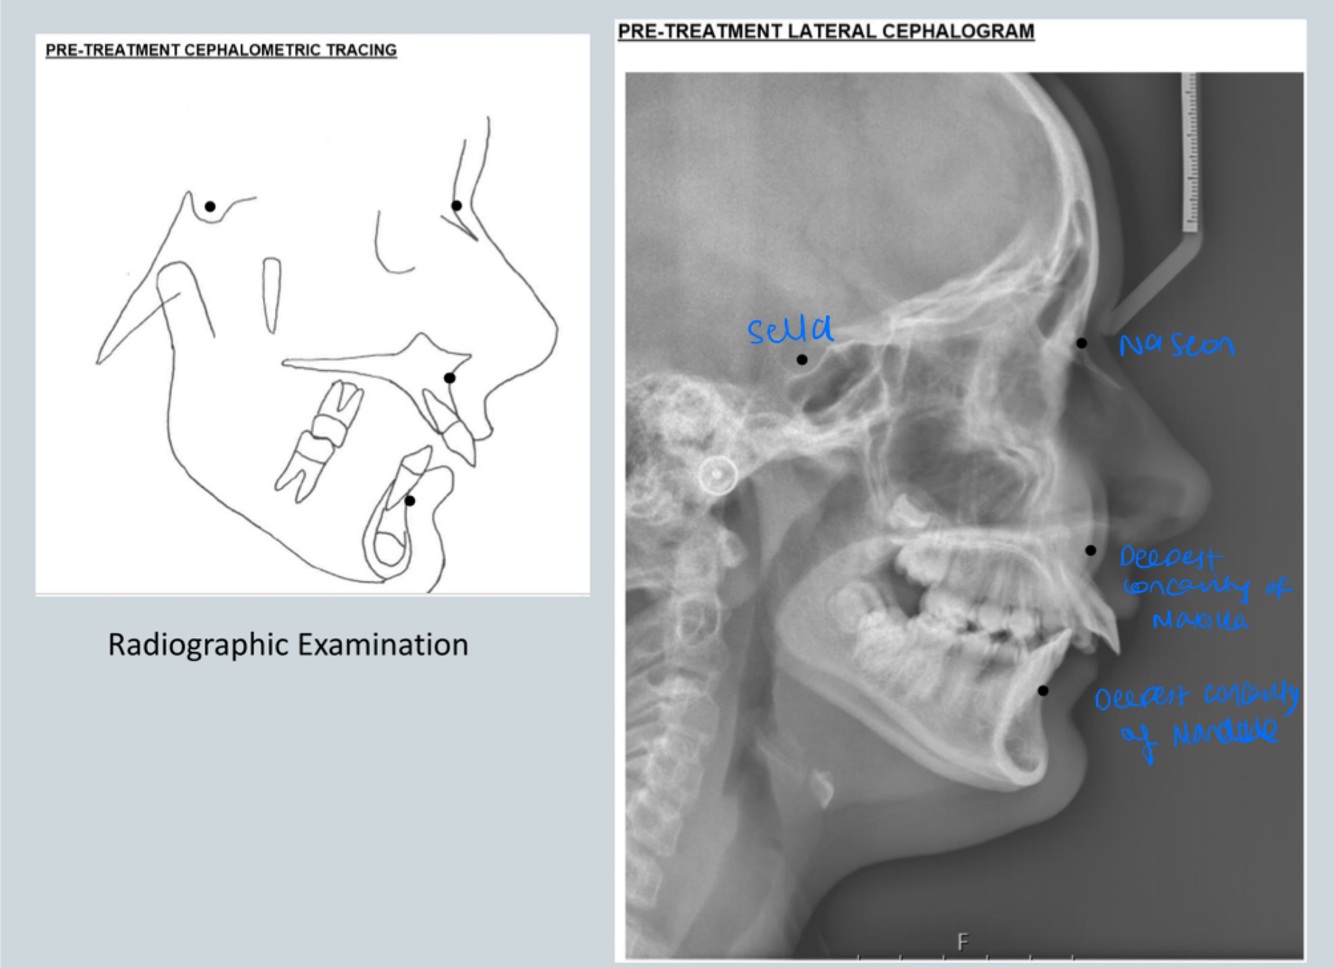

Q

Identify

A

Cephalometric measurements can identify position of upper jaw in relation to cranial base and lower jaw in relationship to cranial base and so relationship of maxilla to mandible

As pt skeletal class II - we can see patients lip trained behind upper incisors and so proclining upper incisors - so this pt has multi factorial aetiology:

- position of maxilla to mandible

- soft tissue trap

10

Class 2 - Angle ANB is :

Analysis of SNB and SNA indicates?

Mandible is retrognathic if it is less than normal SNB

Maxilla is prognathic if it is more than normal SNA

Must check mandible AND maxilla to identify which jaw is causing class II

In this case mandible is in normal position but maxilla is prognathic: